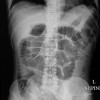

Foto Polos Abdomen

Edukasi pasien pada foto polos abdomen terkait hasil dan indikasi sesuai kondisi abdomen, seperti pada peritonitis, batu saluran kemih, dan ileus. Edukasi pasien pada pemeriksaan foto polos abdomen dapat diberikan sebelum, saat, dan sesudah pemeriksaan. Edukasi meliputi informed consent, persiapan yang perlu dilakukan pasien, posisi pasien, serta follow up setelah pemeriksaan dilakukan.

Sebelum pemeriksaan, pasien perlu diinformasikan pemeriksaan apa yang akan dijalani, risiko akibat radiasi yang dapat terjadi termasuk pada ibu hamil, dan informed consent. Pasien perlu diminta untuk menggunakan gaun pasien dan melepaskan barang–barang radiopaque yang dapat mempengaruhi hasil foto polos abdomen.[1–3]

Edukasi saat pemeriksaan dapat berupa posisi pasien sesuai proyeksi tertentu. Edukasi pasien setelah pemeriksaan berupa hasil pemeriksaan dan follow up yang akan dilakukan. Pasien perlu mengetahui diagnosis yang ditegakkan berdasarkan pemeriksaan foto polos abdomen dan kemungkinan pemeriksaan dengan modalitas pencitraan lain.[1–3,10]